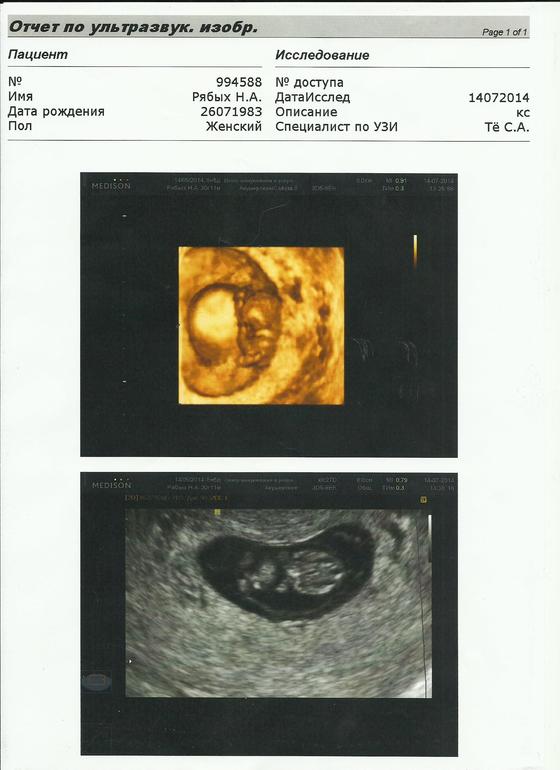

Пришла домой в полном шоке! Потом я написала одной из подруг с ББ и она настоятельно рекомендовала обратиться в ЦИР к Тё Сергею Александровичу! В воскресенье я отправила заявку в электронном виде описав ситуацию а утром ,часов в 8 мне позвонила администратор и сказала, что освободилась запись 13:30 этого же дня )))) Это при том , что как мне сказала подруга у него запись идет за месяц до приема . Мне супер как повезло !Вот резцльтат поездки в ЦИР на Ордынке.

Все ИДИАЛЬНО!!! Волшебное исцеление за 2 дня или первое узи делала уборщица клиники ???

С.А провел мне целую лекцию на эту тему зачитав и указав на якобы неведомый пузырь(со слов первого врача) и жидкости внутри него и пуповина у нас хорошая ,и кислорода хватает! Я показала ему первое узи и он тактично промолчал но при том по фактам своего исследования полностью опроверг его !

НАШЕ ПЕРВОЕ ФОТО